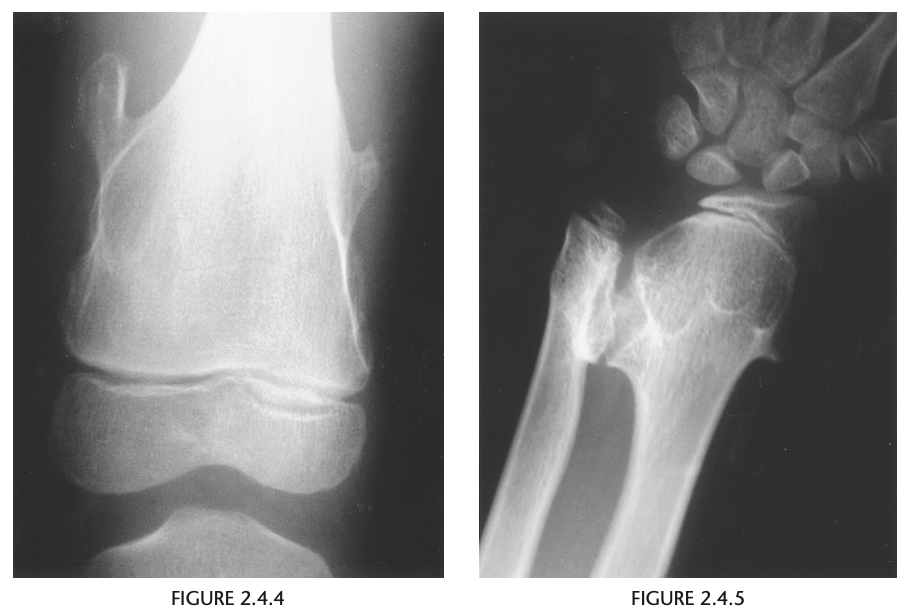

Conventional radiographic findings of an ACL

tear include avulsion fractures from the femoral or

tibial attachment of the ACL (Fig. 2.14.4, arrow), the

Segond fracture (Fig. 2.14.4, arrowhead), or a deep

lateral sulcus sign (Fig. 2.14.5, arrow).

MRI features of the torn ACL include an irregular

or wavy contour with decreased angulation on the

sagittal images (i.e., “lying down” or vertically ori-

ented ACL), increased signal intensity on all MRI

sequences in the region of the ACL (i.e., so-called

“pseudo-mass”), posterior displacement of the lateral

meniscus (i.e., “uncovered lateral meniscus” sign),

loss of the normal obtuse curvature with increased

angulation of the posterior cruciate ligament, undu-

lation of the patellar tendon, and the “empty notch”

sign, which is also seen on arthroscopy.

Bone

impaction from transient subluxation results in

the characteristic osseous contusions involving the posterolateral tibial plateau and midportion of the

lateral femoral condyle (i.e., “kissing contusions”).